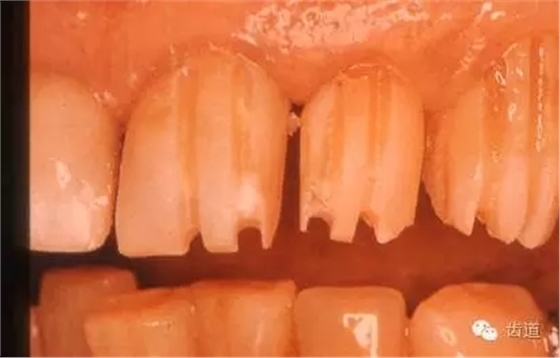

1、切端引導(dǎo)溝:三條,深約1.5-2mm

2、唇面引導(dǎo)溝

平頭柱狀金剛砂車針在唇面預(yù)備三條引導(dǎo)溝,深度約1.2-1.5mm

1、磨除溝間牙體組織:唇面至少預(yù)備1.2mm間隙

2、制備頸緣肩臺(tái)寬1mm,直角或135度